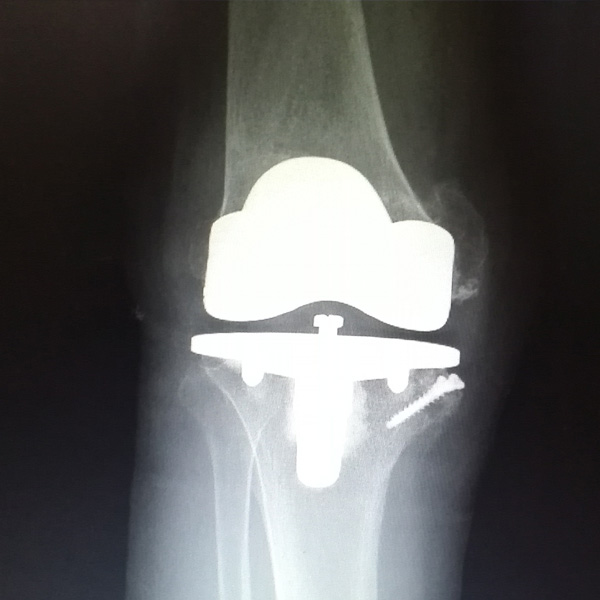

膝關節內翻

患者劉某某,女66歲,左側膝關節嚴重內翻(俗稱的“羅圈腿”),疼痛到不能生活自理。經平臺推薦到哈爾濱醫科大學附屬第二醫院骨關節科就診,......